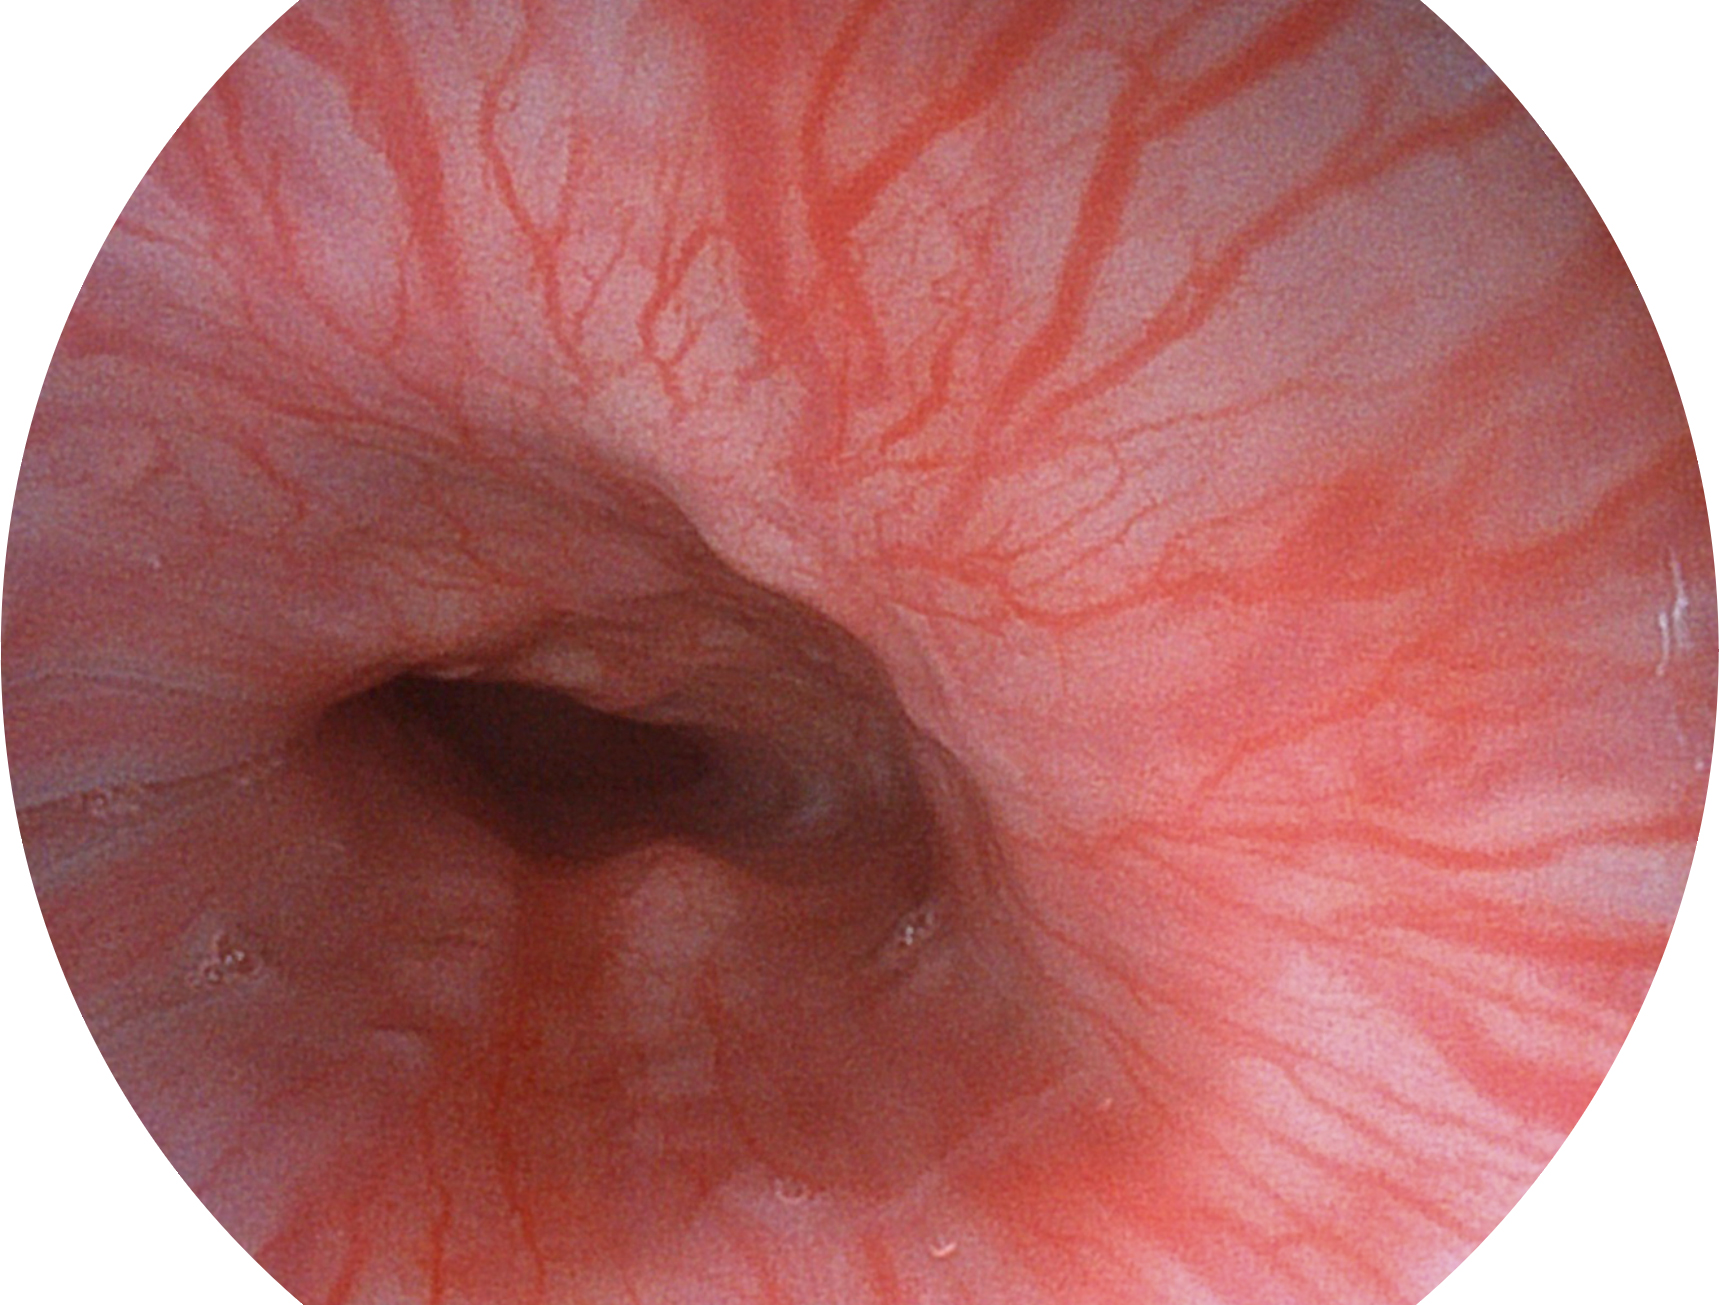

開(kāi)立新開(kāi)發(fā)的內(nèi)鏡染色技術(shù),主要是基于多波長(zhǎng)LED 光源的開(kāi)發(fā),VLS-55Q 四波長(zhǎng)LED 光源是由四個(gè)不同顏色的LED光按照相應(yīng)照明模式所規(guī)定的特定發(fā)光比例進(jìn)行合束后形成,合束后形成的照明光的光譜由紅光、綠光、藍(lán)光及藍(lán)紫光這四個(gè)不同的波段范圍構(gòu)成。具有更高光譜自由度,通過(guò)光譜比例的控制,實(shí)現(xiàn)了聚譜成像技術(shù),英文全稱為“Spectral Focused Imaging, SFI”,縮寫為“SFI”和光電復(fù)合染色成像技術(shù),英文全稱為“Versatile Intelligent Staining Technology, VIST”,縮寫為“VIST”。